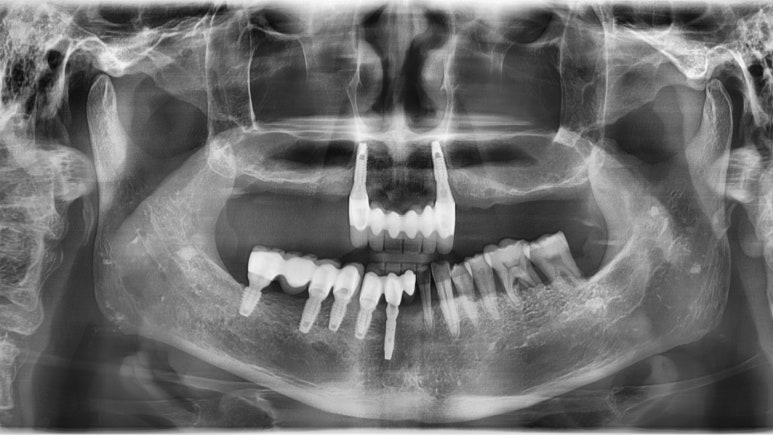

(아래 쪽은 원래 계획대로 진행되어 임플란트5개를 식립하였으며, 위 쪽은 환자가 도중에 2개의 임플란트만 심고 싶어하여 2개의 임플란트 식립)